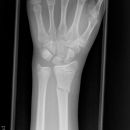

Hand / Handgelenk